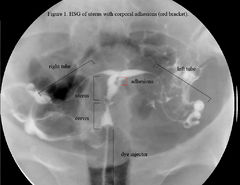

Ashermanův syndrom (AS) je získané onemocnění dělohy, ke kterému dochází, když se uvnitř dělohy a/nebo děložního hrdla vytvoří jizvy (adheze).[1]

Vyznačuje se srůsty zjizvené děložní sliznice (endometria), což zmenšuje objem děložní dutiny. AS může být příčinou poruch menstruace, neplodnosti a abnormalit placenty. Ačkoli první případ nitroděložního srůstu publikoval v roce 1894 Heinrich Fritsch, úplný popis Ashermanova syndromu provedl až po 54 letech Joseph Asherman.